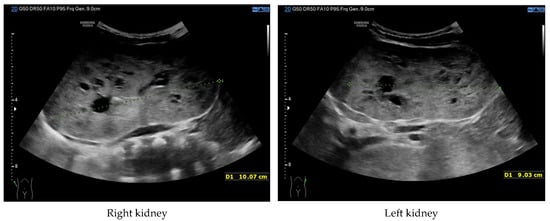

At 4 months of age, the boy was admitted to the hospital due to a hypertensive crisis (BP 162/128 mmHg). Chest X-ray demonstrated cardiomegaly, and echocardiography (ECHO) showed a significant left ventricular hypertrophy and impaired contractility. Abdominal US detected increased kidneys length (right: 101 mm (z-score 8.72); left: 90 mm (z-score 6.59)), with increased echogenicity and loss of corticomedullary differentiation, as well as numerous cysts 5–6 mm in diameter. The liver was enlarged with increased echogenicity with cysts 6–8 mm in diameter (Figure 1 and Figure 2). Doppler US demonstrated high-resistance intrarenal blood flow (RI: 0.75–0.84). Laboratory tests showed microcytic anemia, renal function was assessed as serum creatinine, the glomerular filtration rate (GFR) was estimated according to the Schwartz formula, and liver function was all normal. The boy received multi-drug therapy to control hypertension and heart failure. ECHO, performed after 6 months, was correct.

Figure 2. Ultrasonography of the liver at the age of four months (hyperechogenic, enlarged liver with multiple cysts).